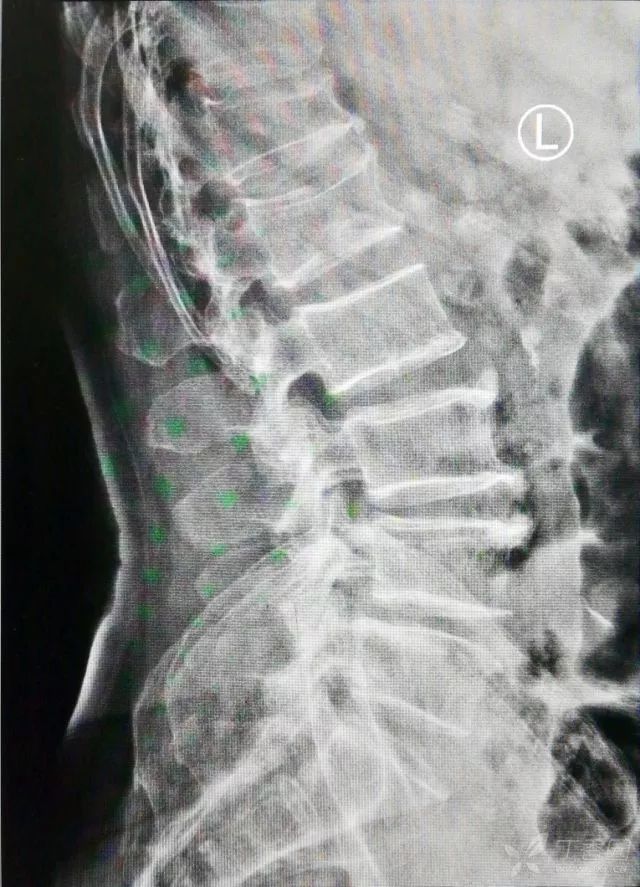

查体:胸腰段压痛阳性,纵向叩击痛阳性。辅助检查:胸 12 椎体陈旧性骨折、腰 1 椎体压缩性骨折,片子如下图。

入院第二天行局麻下腰 1 椎体球囊扩张椎体成形术。